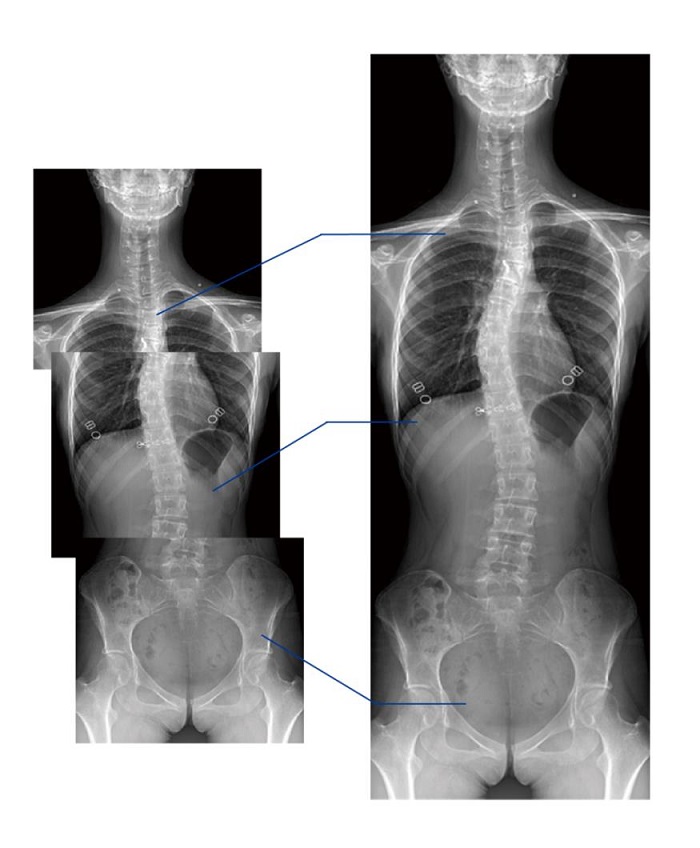

全景拼接功能

全景拼接功能是在全景影像拍攝的情況下,拍攝各個(gè)部位的影像,得到的圖像最終合成一幅全景圖像。適用于輔助脊柱畸形矯形治療、康復(fù)檢查,可對(duì)脊柱、下肢及下肢靜脈造影進(jìn)行分段攝片,然后對(duì)分段圖像進(jìn)行拼接,在一幅X光圖像上完整顯示全脊柱或下肢整體形態(tài),為臨床提供高精度圖像。